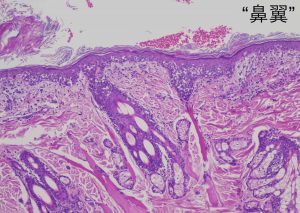

鼻の部位の生検は非常に出血しますので、麻酔が必要ですしコツが必要です。

口唇は歯肉炎もあるので慎重に場所を選びます。

ただの炎症だと良かったのですが、予想通り「上皮向性リンパ腫」でした。これは表皮に限定して増殖するリンパ腫です。そうすると命には影響が少なそうなのですが、大多数のヒトの上皮向性リンパ腫と違って、犬は非常に予後が悪いです。これはヒトでは非常に悪性なグループに分類されるタイプが犬の主流のタイプだからです。